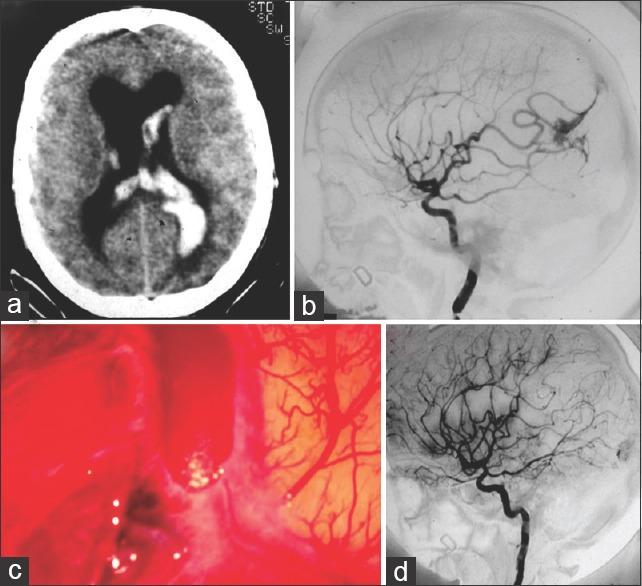

Between 1986 and 2015, 12 pregnant women diagnosed with brain tumors and 17 women with intracranial vascular lesion underwent treatment at the Neurosurgery Department of the Servidores do Estado Hospital and Rede D'Or/São Luis. The Neurosurgery Department teamed up with Obstetrics Anesthesiology Departments in establishing the procedures. The patients' records, surgical descriptions, imaging studies, and histopathological material were reviewed.

Among 12 patients presenting with brain tumors, there were neither operative mortality nor fetal deaths. Among the vascular lesions, aneurysm rupture was responsible for bleeding in 6 instances. Arteriovenous malformation was diagnosed in 7 patients. In this subgroup, the maternal and fetal mortality rates were 11.7% and 23.7%, respectively.

12例脑肿瘤患者中,无手术死亡病例,也无胎儿死亡。在血管病变中,动脉瘤破裂导致6例出血。7例患者诊断为动静脉畸形。在这个亚组中,孕产妇和胎儿死亡率分别为11.7%和23.7%。